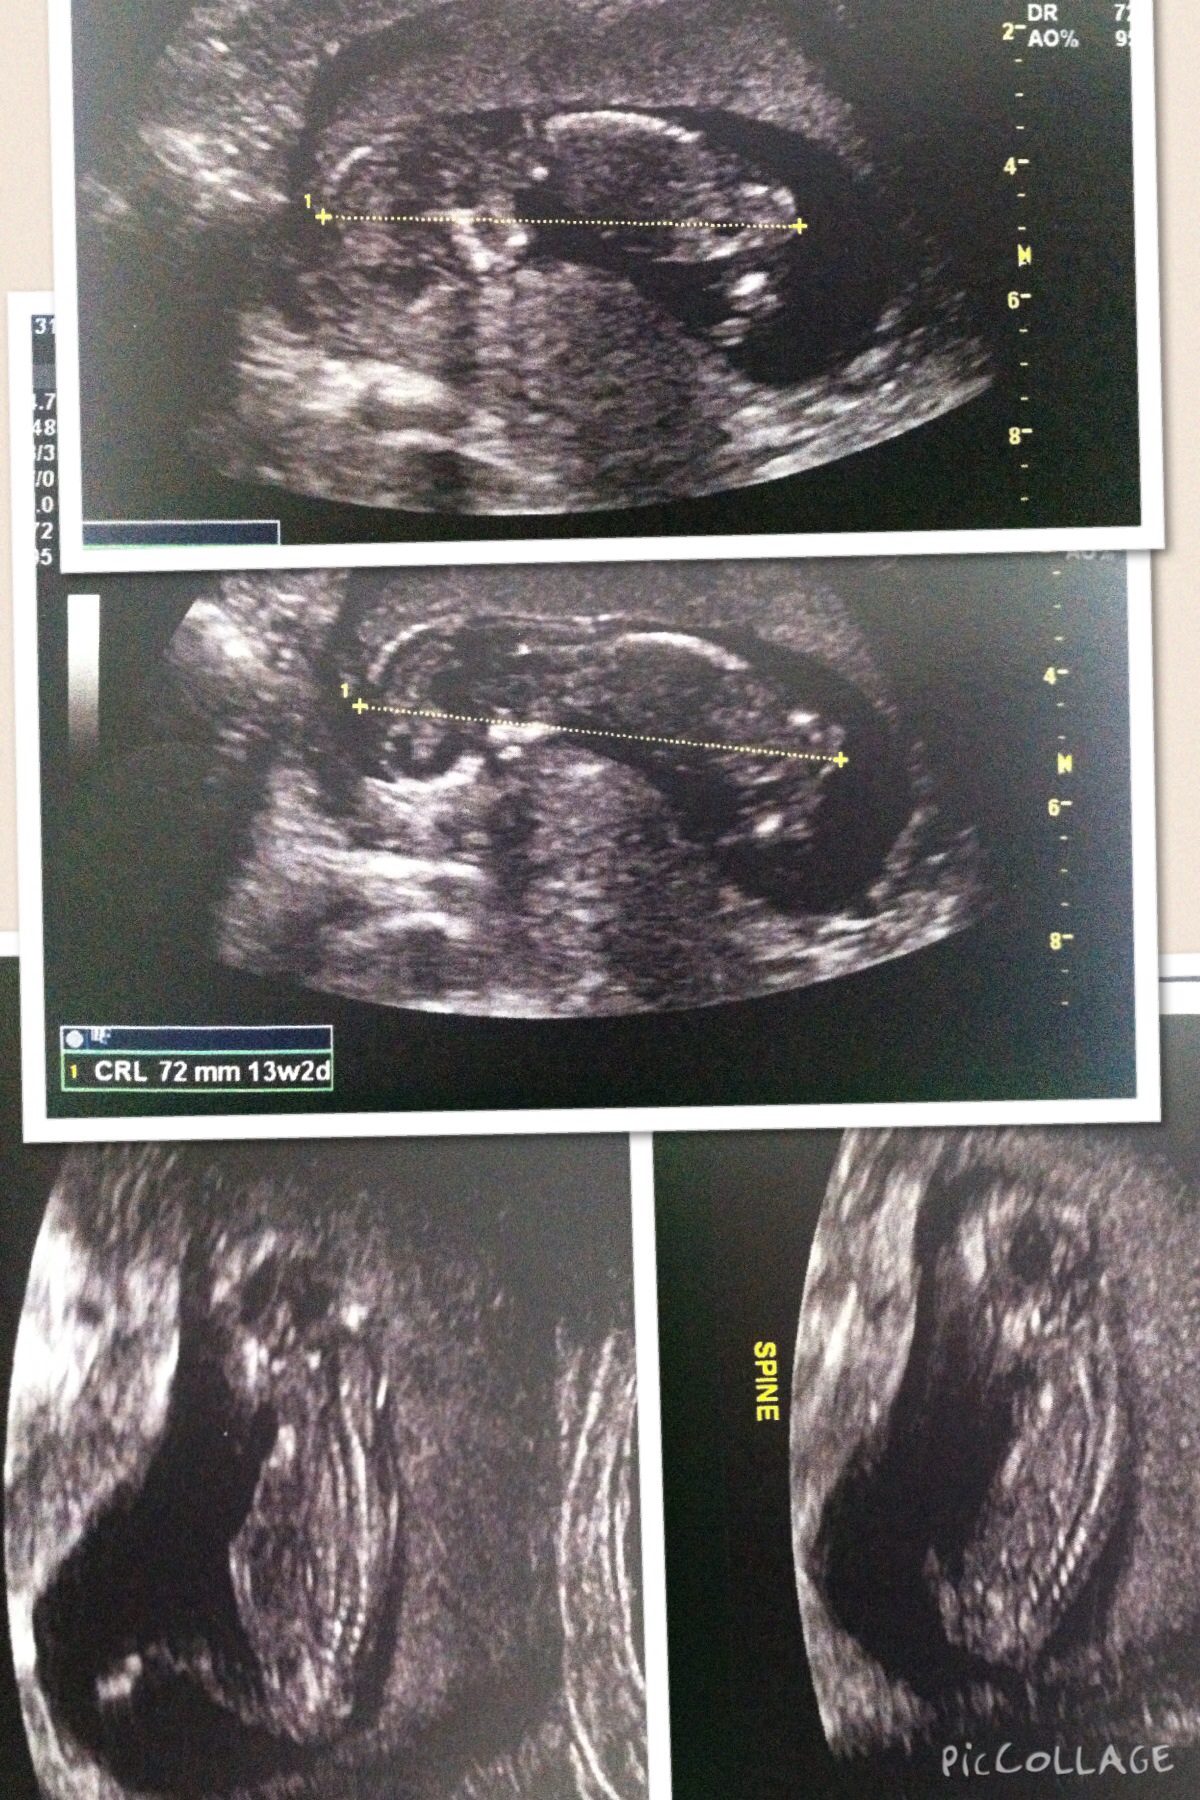

13+1w NT Ultrasound

Hi all! I had my NT sca today and the lady was very unhelpful. When I asked if she knew about the nub theory she went on a big thing about how she didn't believe in it and afterwards whenever she would go anywhere near the nub shot, she would move over or away very quickly so I never got a chance to check it out myself. Quite disappointing but oh well.

I still thought I would give it a go posting here see if anyone can see something I can't otherwise anyone care to guess on skull theory? Attachment 23469Attachment 23470

Just incase they might help, here the rest of the pics that I got... Attachment 23481